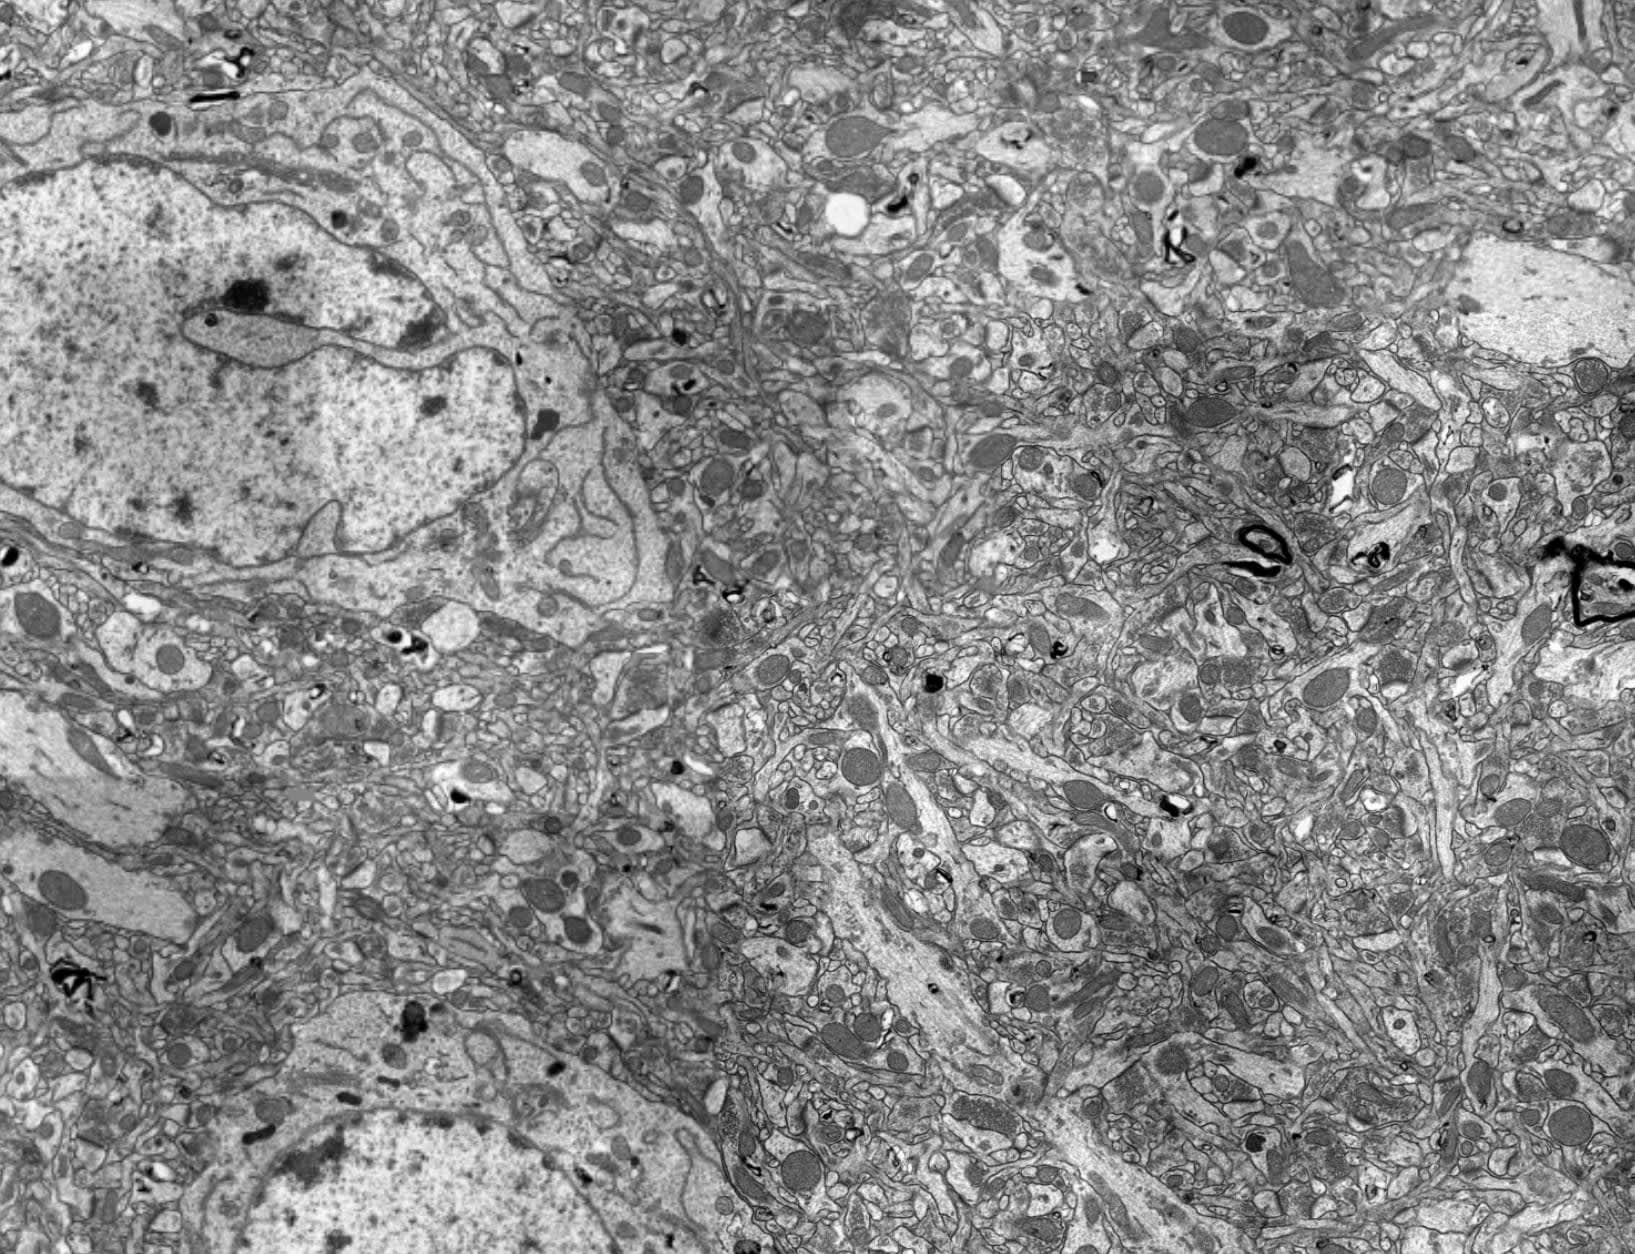

A 3D FIBSEM image of a pig brain preserved post-mortem. We were able to complete surgery in 4 minutes and 30 seconds, well within the critical twelve-minute window, and attained results that appear traceable. Additional results available as supplemental materials. Video linked below:

A H&E stained light microscopy image of a pig cerebellum preserved post-mortem. While the FIBSEM shows good nanostructural preservation, this much lower resolution image shows that a large area of brain is preserved well.

Figure from our preprint. H&E stained light microscopy images from a poorly-preserved brain and a well-preserved brain (E & F, respectively). Note the substantial white regions present in the poorly-preserved tissue on the left. This is strong evidence of inadequate perfusion and compromised preservation. The difference between these two images is only a eight minutes delay in starting preservation.

It took a lot of refinement and expert consultation, but eventually we pinned down the twelve-minute window and blood thinner through a series of experiments on rats. We then streamlined the procedure so it could be done in less than ten minutes on pig carcasses, and finally demonstrated excellent post-mortem preservation in a pig model. We’ve just recently published the results: